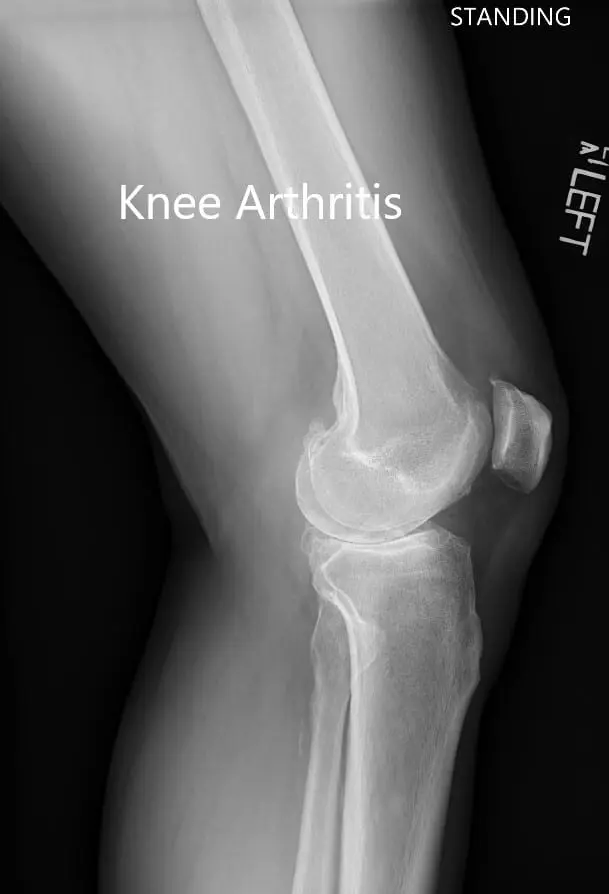

Preoperative X-ray showing the lateral view of the left and the right knee joint

Preoperative X-ray showing the lateral view of the left and the right knee joint- img 2